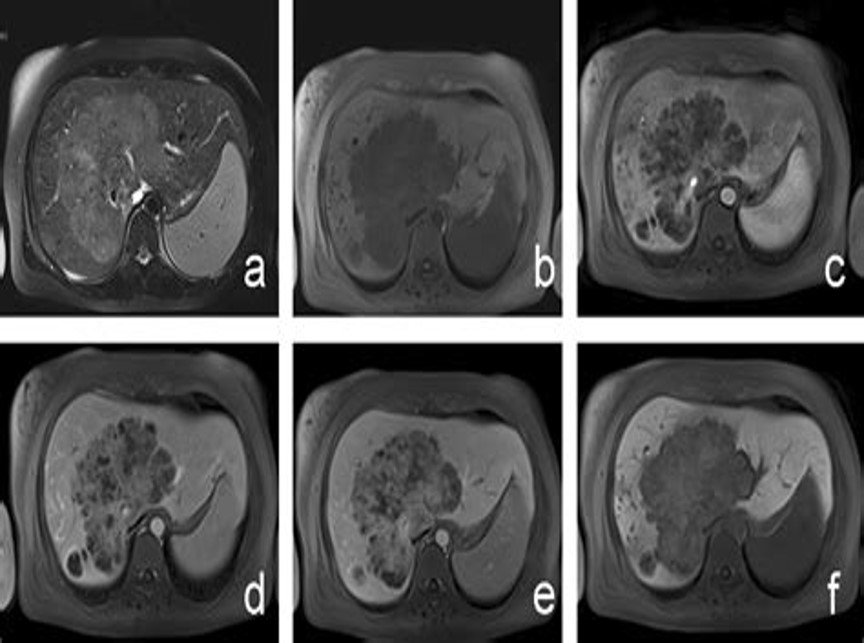

CT and MR images in a 37-year-old male with poorly-differentiated HCC with histological capsule. METAVIR score of the background liver was F3. In contrast-enhanced CT, a 49-mm observation shows (a) nonrim APHE on arterial phase and (b) nonperipheral washout with an enhancing capsule on equilibrium phase. In gadoxetic acid-enhanced MRI, a 48-mm observation shows (c) nonrim APHE on arterial phase, (d) nonperipheral washout on portal venous phase, and (e) TP hypointensity with suspicion of an enhancing capsule on transitional phase. Hepatobiliary phase image clearly shows (f) a nonenhancing capsule surrounding the observation.

T2 :Hypo to slightly hyperintense

Central scar

A 33-year-old male patient with right hepatic haemangiosarcoma. (a) Unenhanced CT image shows a lobulate mass with an indistinct boundary in the right lobe. (b–d) Enhanced CT images of the arterial, venous, and delay phases showed a heterogeneous centripetal enhancement of the mass, and the contrast agent did not completely fill in the lesion at the end.

T1 C+ (Gd)

heterogeneous enhancement with progressive filling

irregular flame-shaped pattern

Target appearance